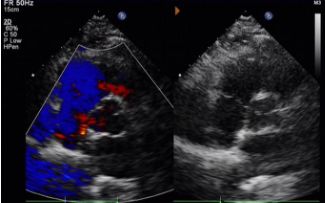

День 1-9 месяцев:

Остаточный шунт не наблюдается.

Постепенное снижение в эхогенности прибора.